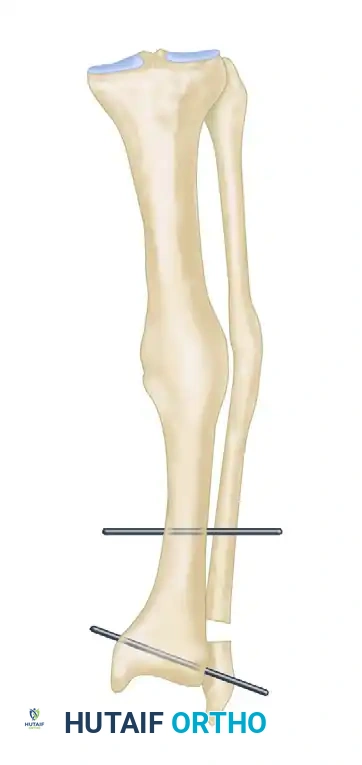

FIGURE 58-11A: Supramalleolar osteotomy. A dome osteotomy is created 1.0 to 1.5 cm proximal to the ankle joint. Threaded pins are inserted parallel to the ankle and knee joint lines.

- Pin Placement for Correction: Under strict fluoroscopic control, insert a 4-mm or 5-mm threaded pin transversely from medial to lateral into the distal tibial fragment, perfectly parallel to the ankle joint line.

- Proximal Pin Placement: Insert a second 4-mm or 5-mm bicortical threaded pin 6 to 10 cm proximal to the osteotomy, ensuring it is perfectly parallel to the knee joint line.

- Osteoclasis and Correction: With a broad osteotome, complete the tibial osteotomy through the posterior cortex. Correct the varus or valgus deformity by manipulating the distal fragment until the two threaded pins are perfectly parallel to one another.